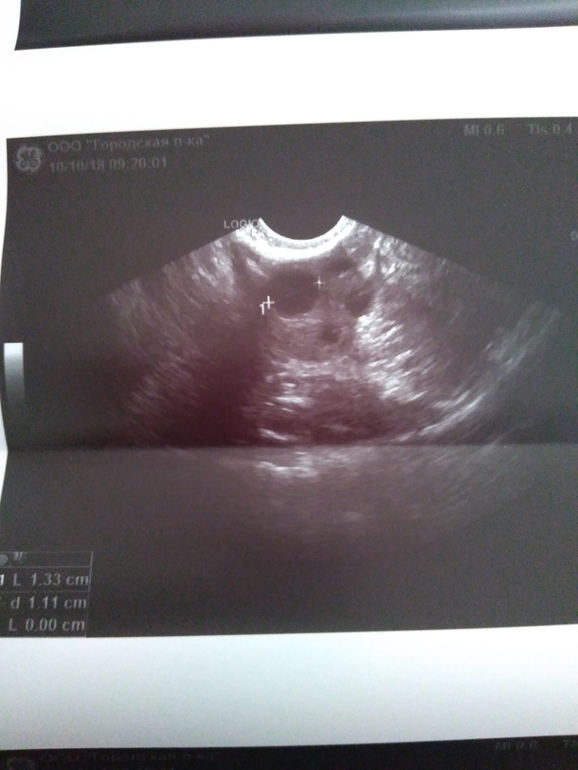

Матка всегда была кзади, теперь почему то кпереди. Может из за фитнеса вчера перевернулась. Или от того,что похудела и ей места больше стало. Сказала матка маловата конечно,но не критично. Эндометрий 5,4 мм ( ошиблись медсестра) на снимке видно. Левый яичник как обычно, а вот в правом ДФ 13,3мм. При длинных циклах сказала нормально. СПКЯ не написала. Сказала яичники не увеличены. Завтра на прием к врачу...